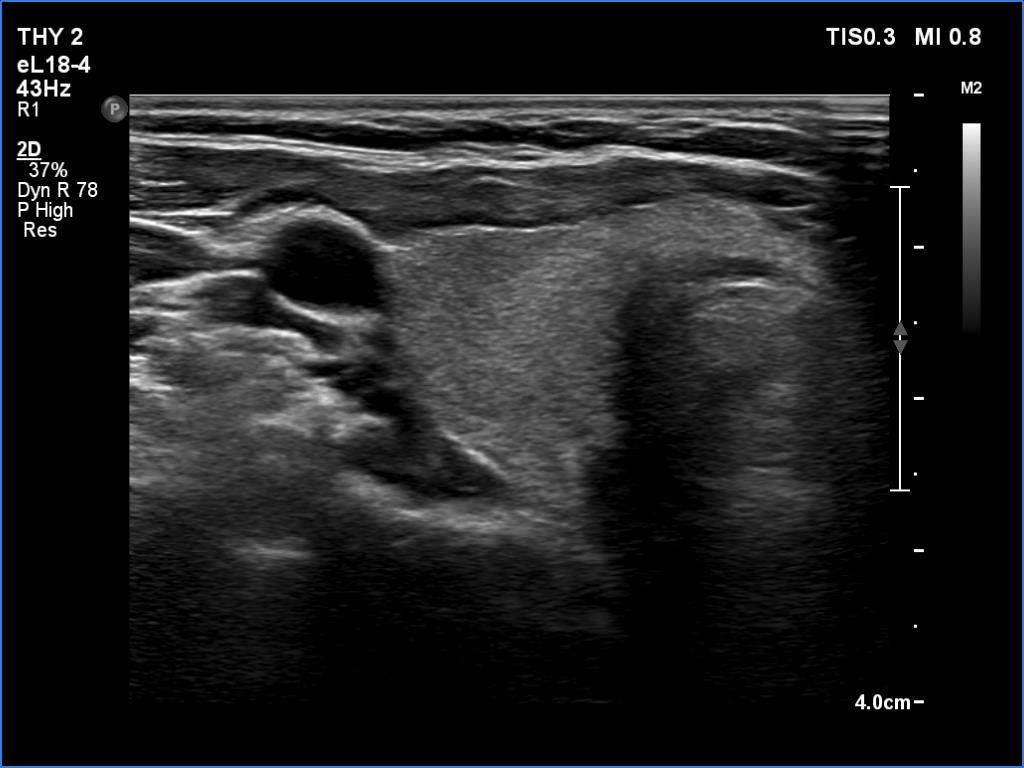

Follow-up 6 months after the first visit (3rd row of images):

Clinical presentation: The patient had no complaints.

Palpation: no abnormality.

Laboratory tests: TSH 2.06 mIU/L, FT4 13.3 pM/L, CRP 0.3 mg/L.

Ultrasonography: The pattern of the entire thyroid became almost completely normal. Only small hypoechoic areas were observed.

Suggestion: TSH in six months, in the event of pregnancy at once.

Follow-up 5 years later (3rd row of images):

Clinical presentation: Six months after the previous visit the patient became pregnant. The TSH was 5.91 mIU/L at the 5th gestational weeks. Replacement therapy was given which was ceased after delivery. The patient was free of complaints and the TSH was in the normal range, even during a next pregnancy 2 years later. Recently, a few weeks after COVID-19 infection, she noticed tenderness in the right side of the neck.

Laboratory tests: TSH 1.72 mIU/L, CRP 3.5 mg/L.

Ultrasonography: The thyroid was intact.